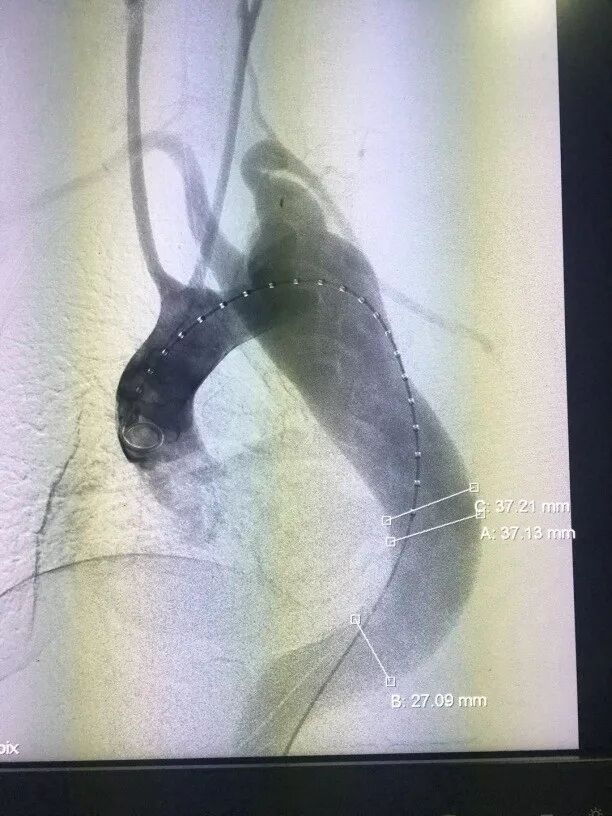

术后造影(图3、图4)和三维重建(图5、图6)显示,支架定位精准,在弓部成角很锐的复杂解剖中支架保持良好形态,基本封堵夹层破口,少量内漏术后继续观察,手术效果良好。

图3 术后造影-病例1

图4 术后造影-病例2